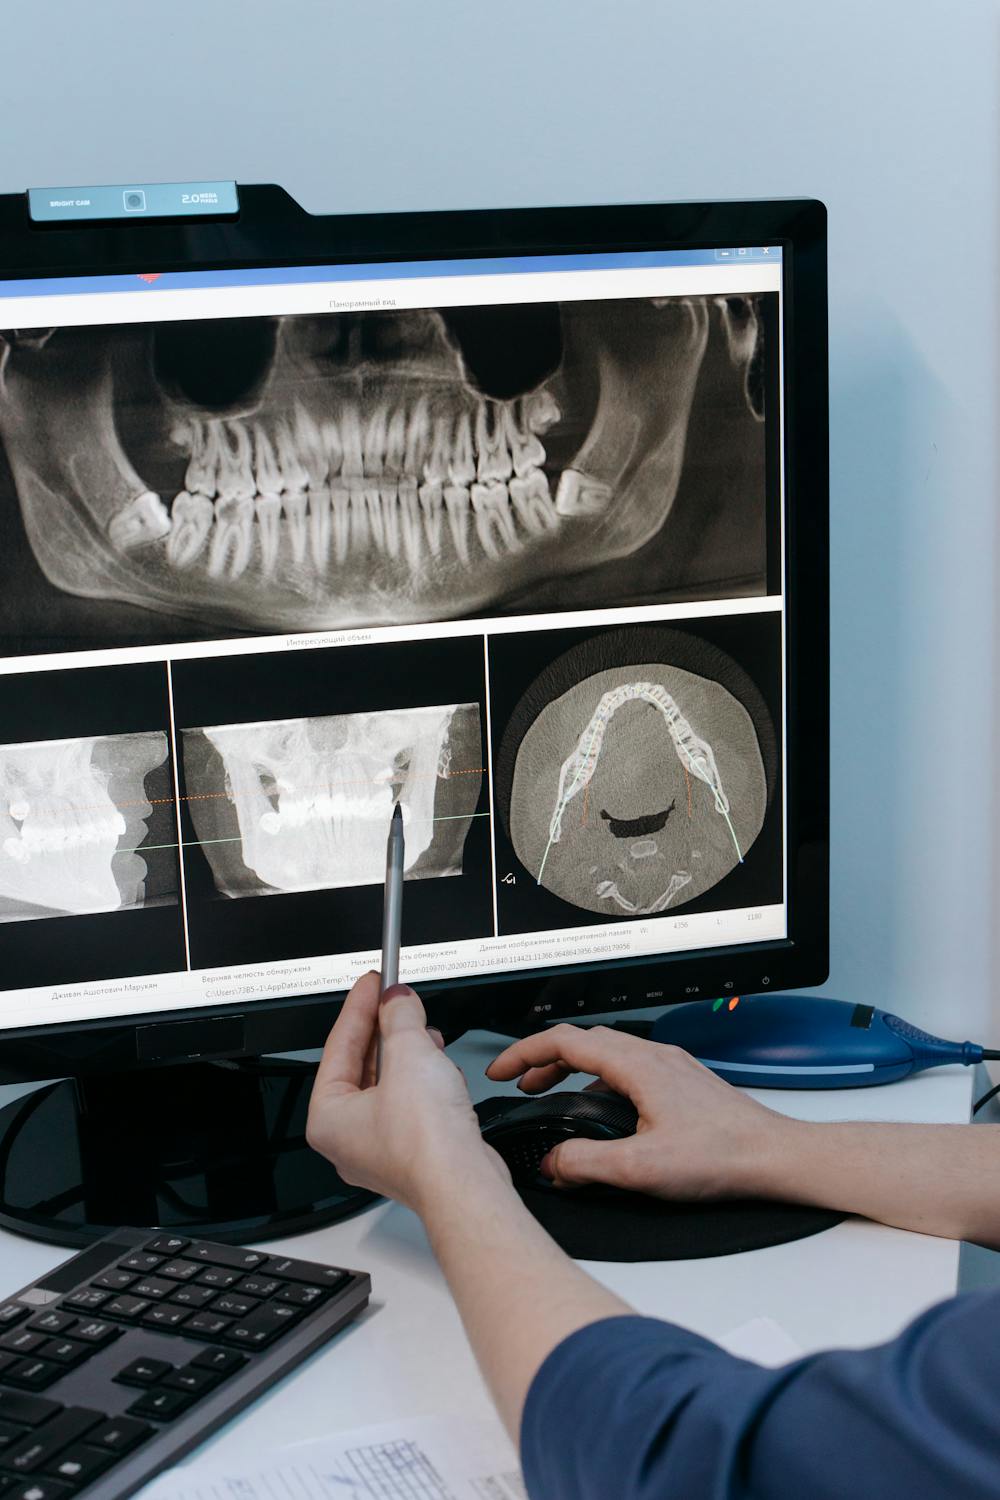

오늘은 턱관절의 기능 이상으로 인해 발생하는 문제로, 턱통증, 귀뚜라미 소리, 턱관절의 제한 등으로 일상생활에서도 상당한 불편을 끼칠 수 있는 턱관절장애에 대하여 알아보겠습니다.

턱관절은 모든 턱운동의 중심축으로 작용하며 턱 근육과 인대에 의해 지지 되는데, 이때 턱관절 사이에 있는 디스크는 뼈와 뼈 사이의 쿠션 역할을 하게 되며 이러한 근육과 인대, 디스크, 턱뼈가 함께 어우러져 개구(입 벌리기)와, 저작(씹는 행위), 말하기, 삼키기 등의 복합적인 활동을 담당하게 되는데, 여러 요인에 의해 이러한 턱관절 기능에 이상이 생긴 것을 턱관절 장애 또는 악관절 장애라고 합니다.

3. 턱관절장애의 증상

턱관절 장애의 대표적인 증상으로 통증을 들 수 있는데, 음식을 씹거나 하품할 때 양쪽 귀 앞의 아래턱뼈와 저작 근육에 통증을 느끼게 되며 또한 입을 열 때마다 턱 관절에서 소리가 나며(관절 잡음), 입과 턱의 움직임이 제한되어 집니다(하악운동 제한).